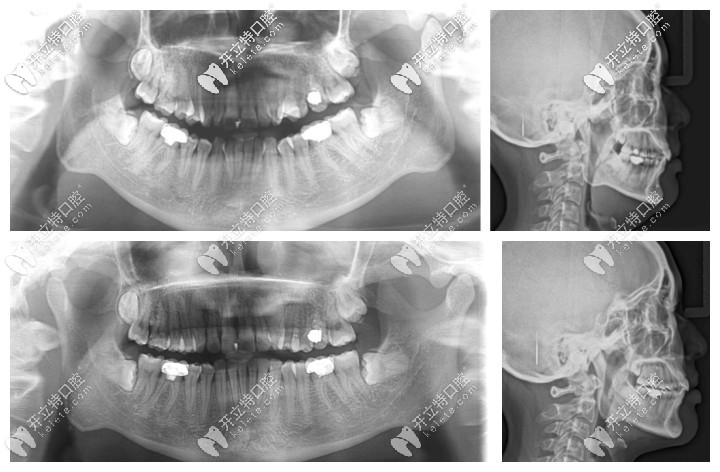

深覆合矯正前后的CT片